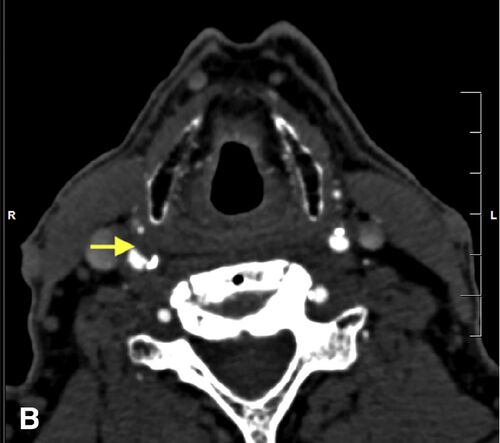

症例59:一過性の無痛性右視力低下を訴える65歳男性 (J Emerg Med. 2020 Dec 1;S0736-4679(20)31057-X.)

病歴/身体所見 ・65歳男性 ・突然発症/無痛性の右眼視力低下が、6か月に3回ほど認められていた ◦視野が灰色になるようだと表現する ◦それぞれ60-90秒ほどの持続時間 ・GCAを疑わせる症状はなく、そのほかの神経学的異常の所見なし ・高血圧/脂質異常症/糖尿…